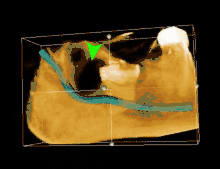

3D CT لضرس العقل المنطمر المتاخم للعصب السنخي السفلي قبل خلعه 3D CT لضرس العقل المنطمر المتاخم للعصب السنخي السفلي قبل خلعه | |